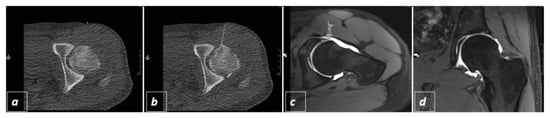

Evaluation of CT-Guided Ultra-Low-Dose Protocol for Injection Guidance in Preparation of MR-Arthrography of the Shoulder and Hip Joints in Comparison to Conventional and Low-Dose Protocols

2.2. CT-Guided Joint Injections

2.3. The Three Different Examination Protocols